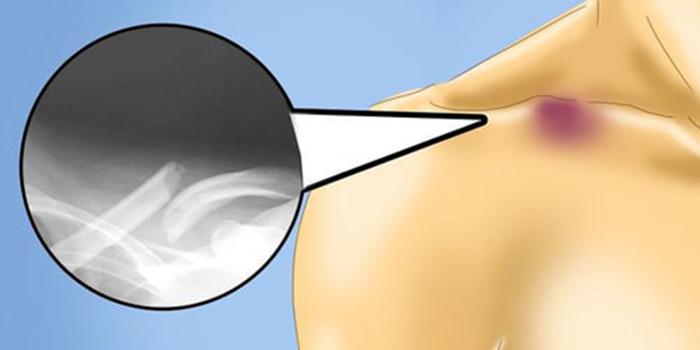

Для начала врач проводит осмотр и собирает анамнез, чтобы выяснить, как произошла травма. Затем необходимо сделать рентгеновский снимок, чтобы подтвердить диагноз и определить тип перелома. В некоторых случаях может потребоваться КТ или МРТ для более детального обследования.

Такую травму медики могут заметить уже в родовом зале: наблюдается деформация ключицы, ребенок может проявлять беспокойство и плакать при пальпации. Подтверждение диагноза происходит с помощью рентгенографии.

Определить перелом ключицы несложно, поскольку она расположена близко к поверхности кожи. Часто смещение отломков видно невооруженным глазом. При осмотре можно заметить укорочение надплечья с поврежденной стороны. Однако у детей первого года жизни чаще наблюдаются неполные переломы этой кости.

Таким образом, переломы могут происходить без повреждения надкостницы. Врачи-травматологи определяют такие травмы как «зеленые ветки»: сгибая их пополам, внутренний стержень ломается, но оболочка остается целой, что не позволяет двигаться концам. Перелом присутствует, но нет явных деформаций.

При таком раскладе диагностировать травму сложнее, хотя боли и синяки могут проявляться, функция конечности может нарушаться, но болезненные ощущения минимальны. Ребенок может не придавать этому значения. Родители также могут не заметить или объяснить симптомы как обычный ушиб. Лишь когда появляется плотное образование в месте срастающегося перелома к концу недельного срока, родители могут решить обратиться к врачу, который его направит на рентген для определения местоположения перелома и возможного смещения отломков.